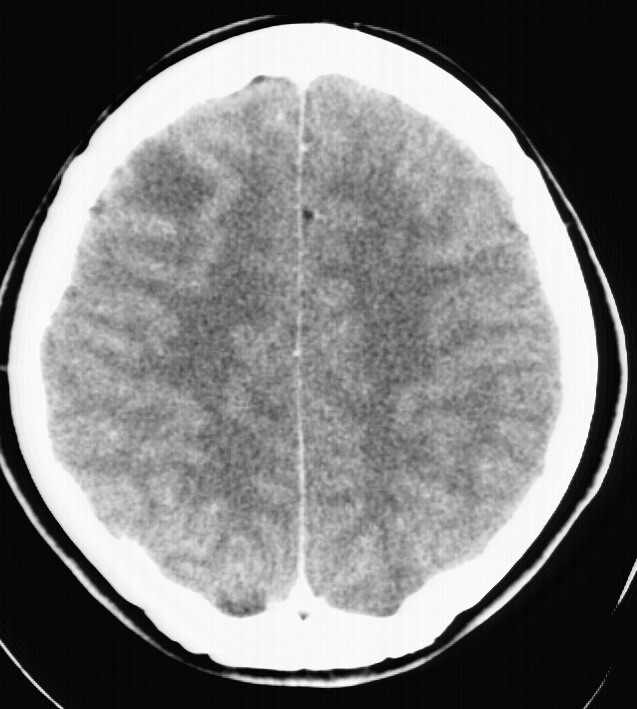

标题: CT5853:右额叶上部占位请会诊

女,34岁,自述头晕胀2年,近期感精神恍惚,无发热,实验室检查阴性。

右顶叶靠近脑表面圆形低密度灶,周围无水肿及占位效应,增强病灶无明显强化,考虑:右顶叶低分级星型细胞瘤。

右额叶上部皮质区见类圆形低密度区,边界不清,无强化,无钙化。

支持大多数战友的意见,1级星形细胞瘤。